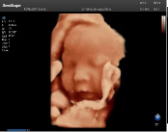

4容積探頭

積探頭是在二維圖像的基礎(chǔ)上,將連續(xù)采集的空間分布位置,經(jīng)過計算機(jī)重建算法,從而獲得完整的空間形態(tài)。

適用于:胎兒面部、脊柱和肢體等。

優(yōu)勢特點:快速獲取、掃查連續(xù)均勻、解剖結(jié)構(gòu)顯示為容積數(shù)據(jù)、準(zhǔn)確進(jìn)行容積測量。